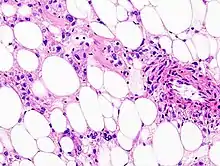

| Histopathologic image of renal angiomyolipoma. Nephrectomy specimen. H&E stain. | |

PECs consist of perivascular epithelioid cells with a clear/granular cytoplasm and central round nucleus without prominent nucleoli.